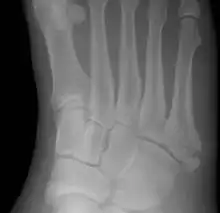

![]() | |

| Jones fracture as seen on Xray | |

A Jones fracture is a break between the base and middle part of the fifth metatarsal of the foot.[9] It results in pain near the midportion of the foot on the outside.[2] There may also be bruising and difficulty walking.[3] Onset is generally sudden.[4]

The fracture typically occurs when the toes are pointed and the foot bends inwards.[2][6] This movement may occur when changing direction while the heel is off the ground such in dancing, tennis, or basketball.[10][11] Diagnosis is generally suspected based on symptoms and confirmed with X-rays.[3]